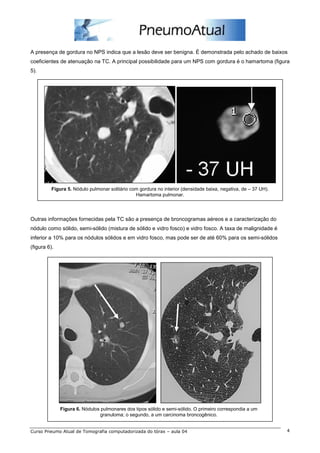

A presença de gordura no NPS indica que a lesão deve ser benigna. É demonstrada pelo achado de baixos

coeficientes de atenuação na TC. A principal possibilidade para um NPS com gordura é o hamartoma (figura

5).

Figura 5. Nódulo pulmonar solitário com gordura no interior (densidade baixa, negativa, de – 37 UH).

Hamartoma pulmonar.

Outras informações fornecidas pela TC são a presença de broncogramas aéreos e a caracterização do

nódulo como sólido, semi-sólido (mistura de sólido e vidro fosco) e vidro fosco. A taxa de malignidade é

inferior a 10% para os nódulos sólidos e em vidro fosco, mas pode ser de até 60% para os semi-sólidos

(figura 6).

Figura 6. Nódulos pulmonares dos tipos sólido e semi-sólido. O primeiro correspondia a um

granuloma; o segundo, a um carcinoma broncogênico.